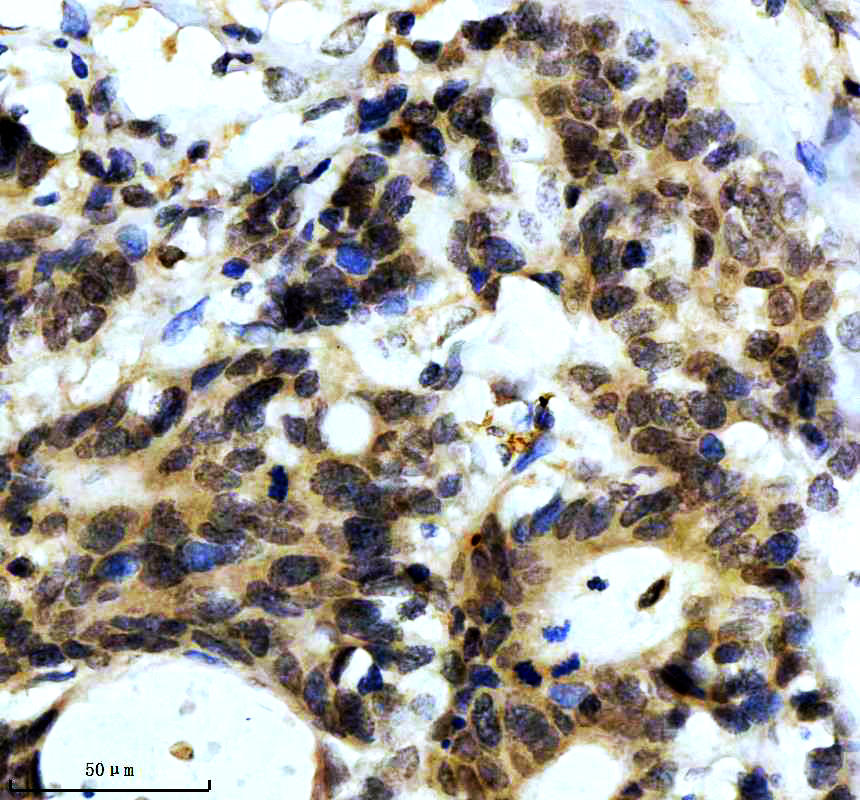

IHC analysis of SNCA using anti-SNCA antibody (BM4024) .

SNCA was detected in a paraffin-embedded section of human glioma tissue. The tissue section was incubated with rabbit anti-SNCA Antibody (BM4024) at a dilution of 1:200 and developed using HRP Conjugated Rabbit IgG Super Vision Assay Kit (Catalog # SV0002) with DAB (Catalog # AR1027) as the chromogen.